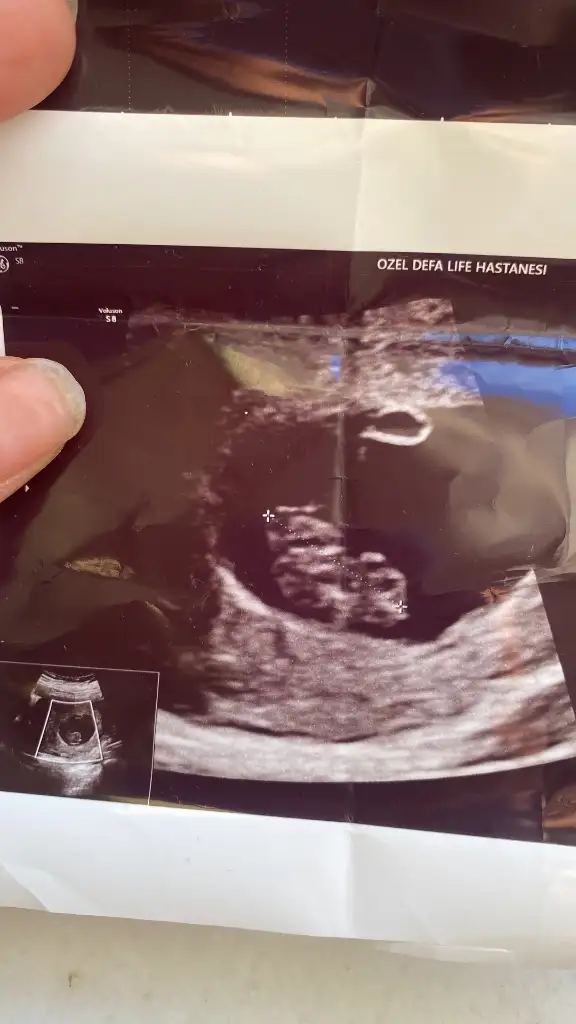

Nub veya Ramzi Theorisi anlayan var mı?

Ramzi teorisi için daha küçük haftalardaki yani bebeğin kese içindeki yerleşimine göre bakıyorlar diye biliyorum. 7 ,8 haftalar gibi.

Burda ise eğer gördüğüm nub ise kız bebek tahminim. Gönlünüzce olur umarım 🙏

Benimkinede bakar mısın rica edersem